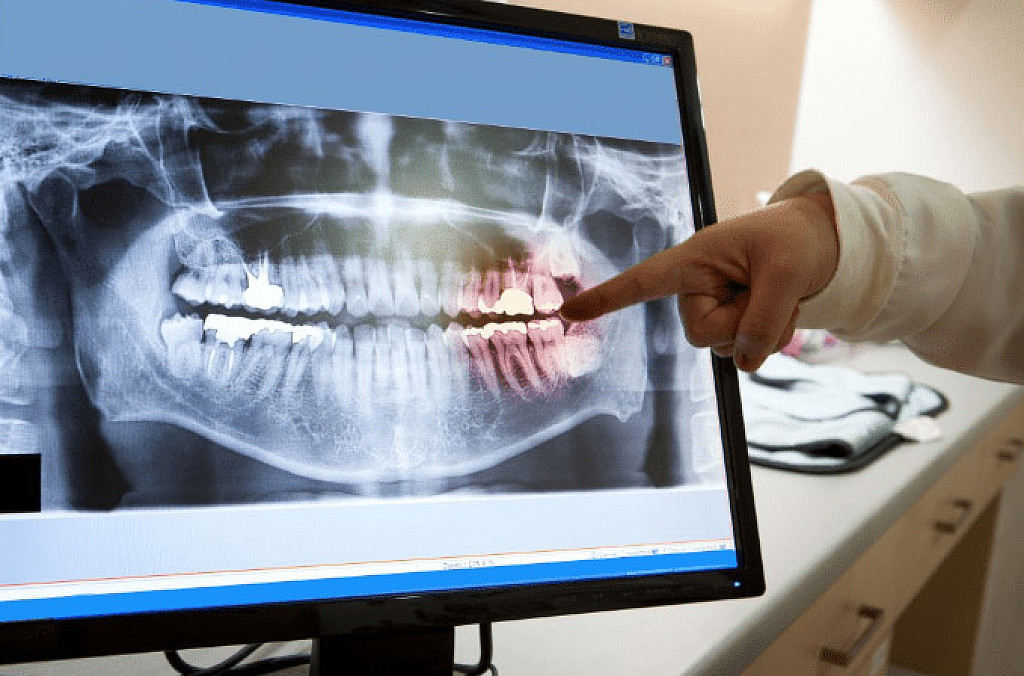

A simple oral exam only allows a dentist to see the visible surfaces of the teeth and the insides of the oral cavity. With the help of an X-ray, dentists can visualize the structures present within the tooth cavity as well as the supporting bone. This allows them to detect and treat dental issues that may otherwise remain undiagnosed and lead to more problems.

Panoramic X-Ray:  This is a type of sizeable dental X-ray that requires a separate machine. The X-ray provides a detailed image of all the teeth in both lower and upper arches, along with the bone and supporting structures. They are usually used for extensive dental work like multiple extractions, braces, dental implants, etc.